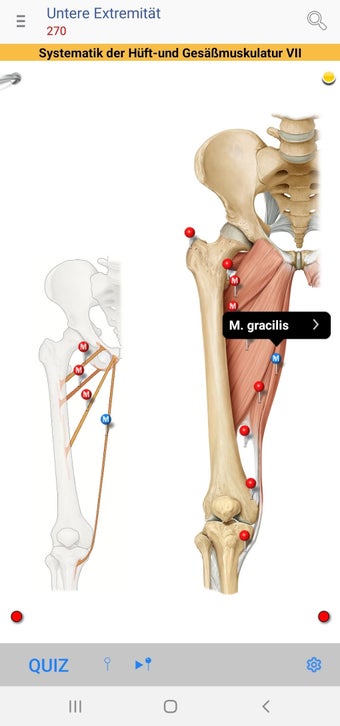

The app consists of different sections, each of which contains information about a specific part of the body. You will learn about the different organs, as well as the muscles, bones, and other important structures. You can test yourself with a unique quiz that consists of multiple-choice questions.

The app allows you to learn about the body in a simple and fun way, and to test yourself in a quick and easy way.